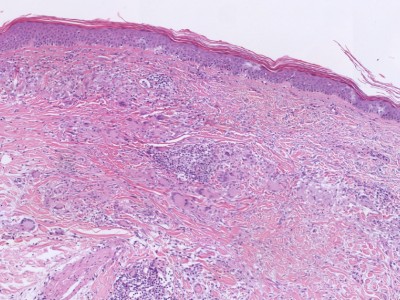

PA:De epidermis is normaal. In de dermis focale degeneratie van collageen met een reactieve ontsteking en fibrose. Soms meerkernige reuscellen. In de dermis een superficieel en diep perivasculair en interstitieel gelegen ontstekingsinfiltraat. Dit infiltraat is samengesteld uit histiocyten, lymfocyten en plasmacellen. Opvallend is de aanwezigheid van necrobiosis omgeven door een wal van histiocyten en lymfocyten. De necrobiotische zone kleurt aan met Alcian blue.